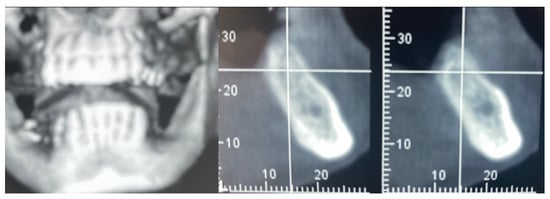

A 61-year-old female patient came to our attention. The clinical evaluation revealed a severe atrophic ridge in the left posterior mandible (Figure 2a). The patient stated that the teeth were extracted 5 years before and the first bicuspid only a month before the consultation. The radiographic evaluation showed the presence of a residual root fragment (Figure 2b). It was also possible to observe the radiolucency of the healing socket of the first bicuspid. The patient was further evaluated with a CBCT to complete the case documentation and data collection. The CBCT showed a severely atrophic ridge with an unfavorable anatomy for dental implant insertion (Figure 3).

Figure 3.

CBCT at baseline: (a) volumetric reconstruction of the edentulous area; (b) cross-section of the area.

3.4. Implant Insertion

In this case of important bone augmentation, a healing period of 8 months was observed. Indeed, biomaterials, such as FCS, require a longer time than autogenous bone. No complications were experienced during the follow-up. At the end of the healing period, CBCT was performed to plan the implants’ insertion (Figure 8). It was pleasant to observe that the GBR provided the desired volume augmentation for the ridge. The CBCT showed a horizontal and vertical ridge augmentation of 8 mm and 8 mm, respectively.

Figure 8.

New volume observed 8 months after surgery.